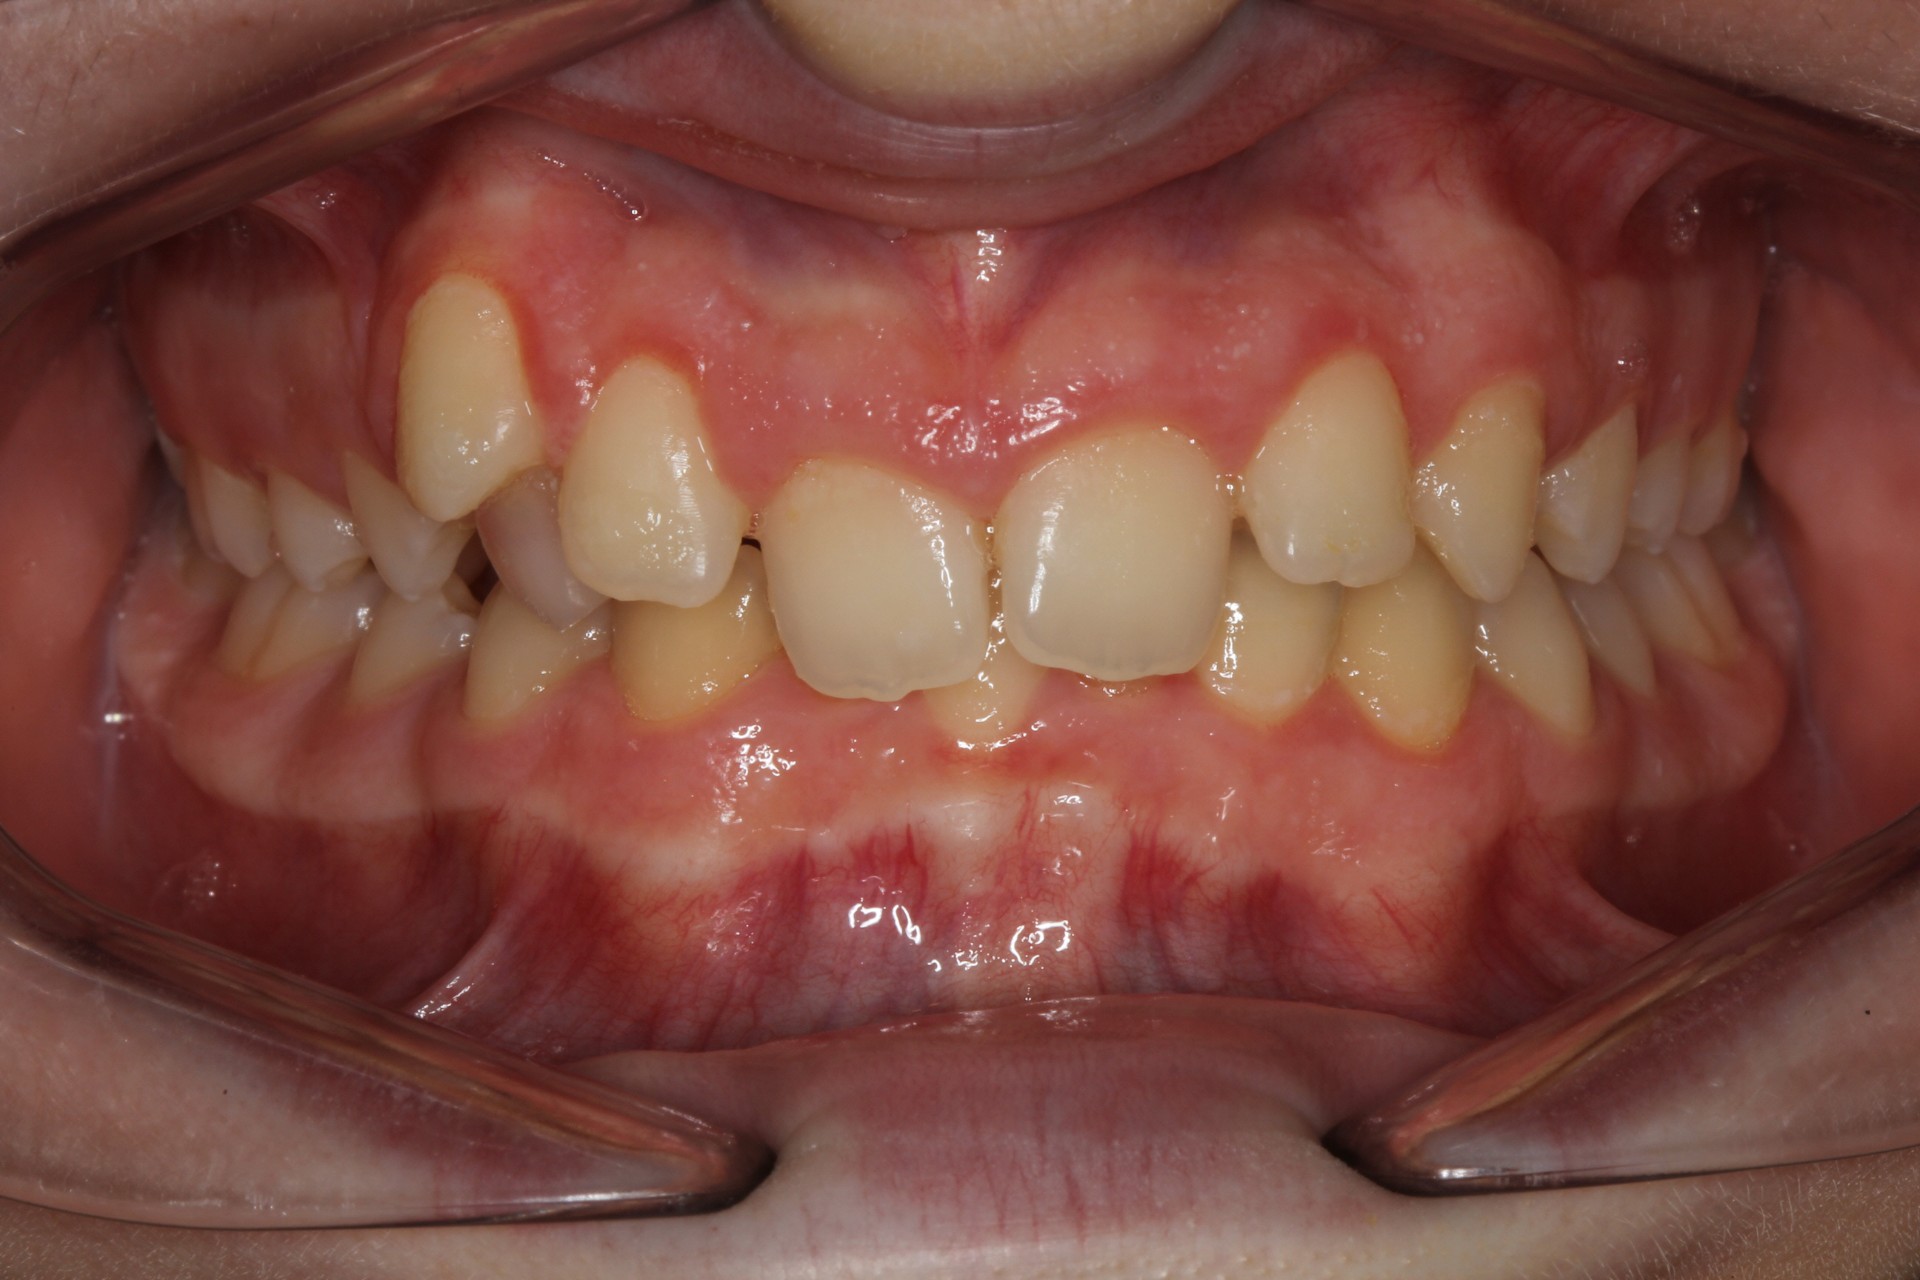

Crowding with lateral open bite – Child case